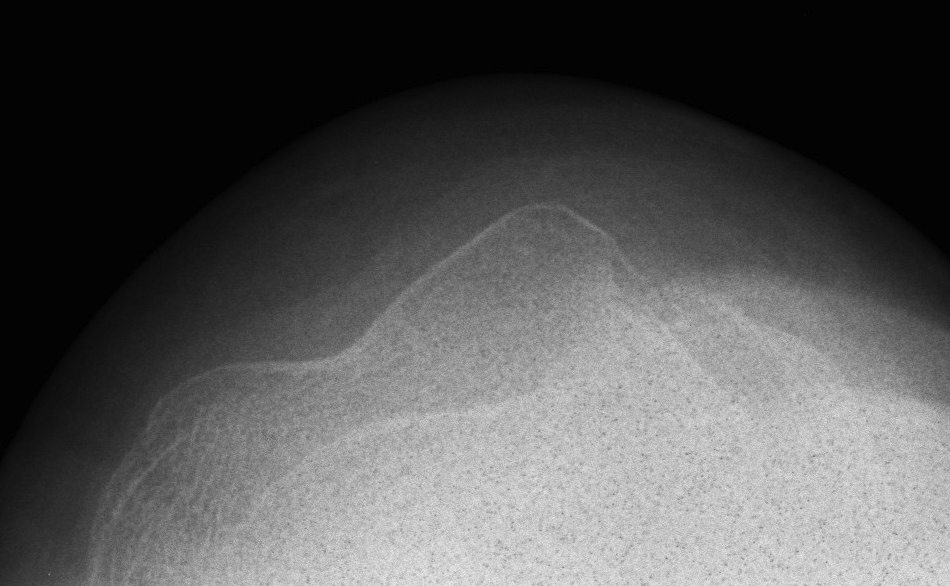

Xray

Look for osteochondral fractures

- skyline xray: suprapatella pouch

Osteochondral fracture visible on skyline view